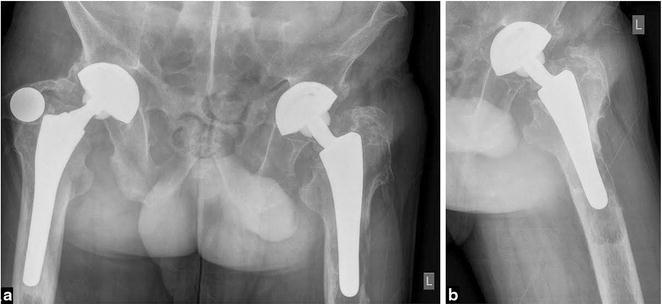

The authors describe clinical and radiologic features, histologic appearance, and treatment of osteogenic osteosarcoma located in the proximal femoral diaphysis associated with an unstable femoral prosthesis following THA in a 65-year-old male patient. The patient with HLA-B27 positive ankylosing spondylitis underwent arthroplasty 15 years ago.

The neoplastic process may be considered as an extraordinary complication of THA and might just be coincidental or the result of some derangement of the healing process in host tissue with no definitely proven hypothesis that the implants or their by-products are carcinogenic. The soluble chemical substances from the implanted prosthetic material are, at least in animals, suspected to play a vital role in the pathogenesis of the neoplastic transformation of the bone tissue. The presented case shall alert orthopedic surgeons to clinical, radiologic, and macroscopic similarities between a malignant tumor and benign lesions caused by wear debris at THA sites. At the examination of plane X-rays of patients with THA loosening, the differential diagnosis should always include osteogenic sarcoma, as well. To our knowledge, there have been only nine cases of THA-related osteogenic osteosarcomas described in the English-language literature.